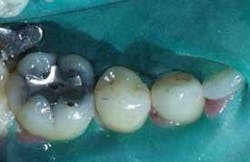

Although nanohybrids are universal in use for anterior and posterior restorations, I have chosen to illustrate a multisurface molar restoration. Strength and adhesive properties of nanohybrids make them ideal for repair of posterior as well as anterior teeth.

A patient's large amalgam was failing in a lower right first molar (Fig. 1). This was removed, creating a considerable residual defect. Traditionally, the option of a crown buildup, combined with a lab processed restoration, may be recommended. In our office, we use digital photography to consult with patients, showing images of their condition along with treatment solutions. We offer choices of solutions used for other patients with similar needs.

Due to wear and esthetic characteristics, the final restoration blends in esthetically, feels natural, and adhesively strengthens the tooth (Fig. 3). Our patient valued that it was completed in one visit, minimized tooth removal, and saved immediate costs.